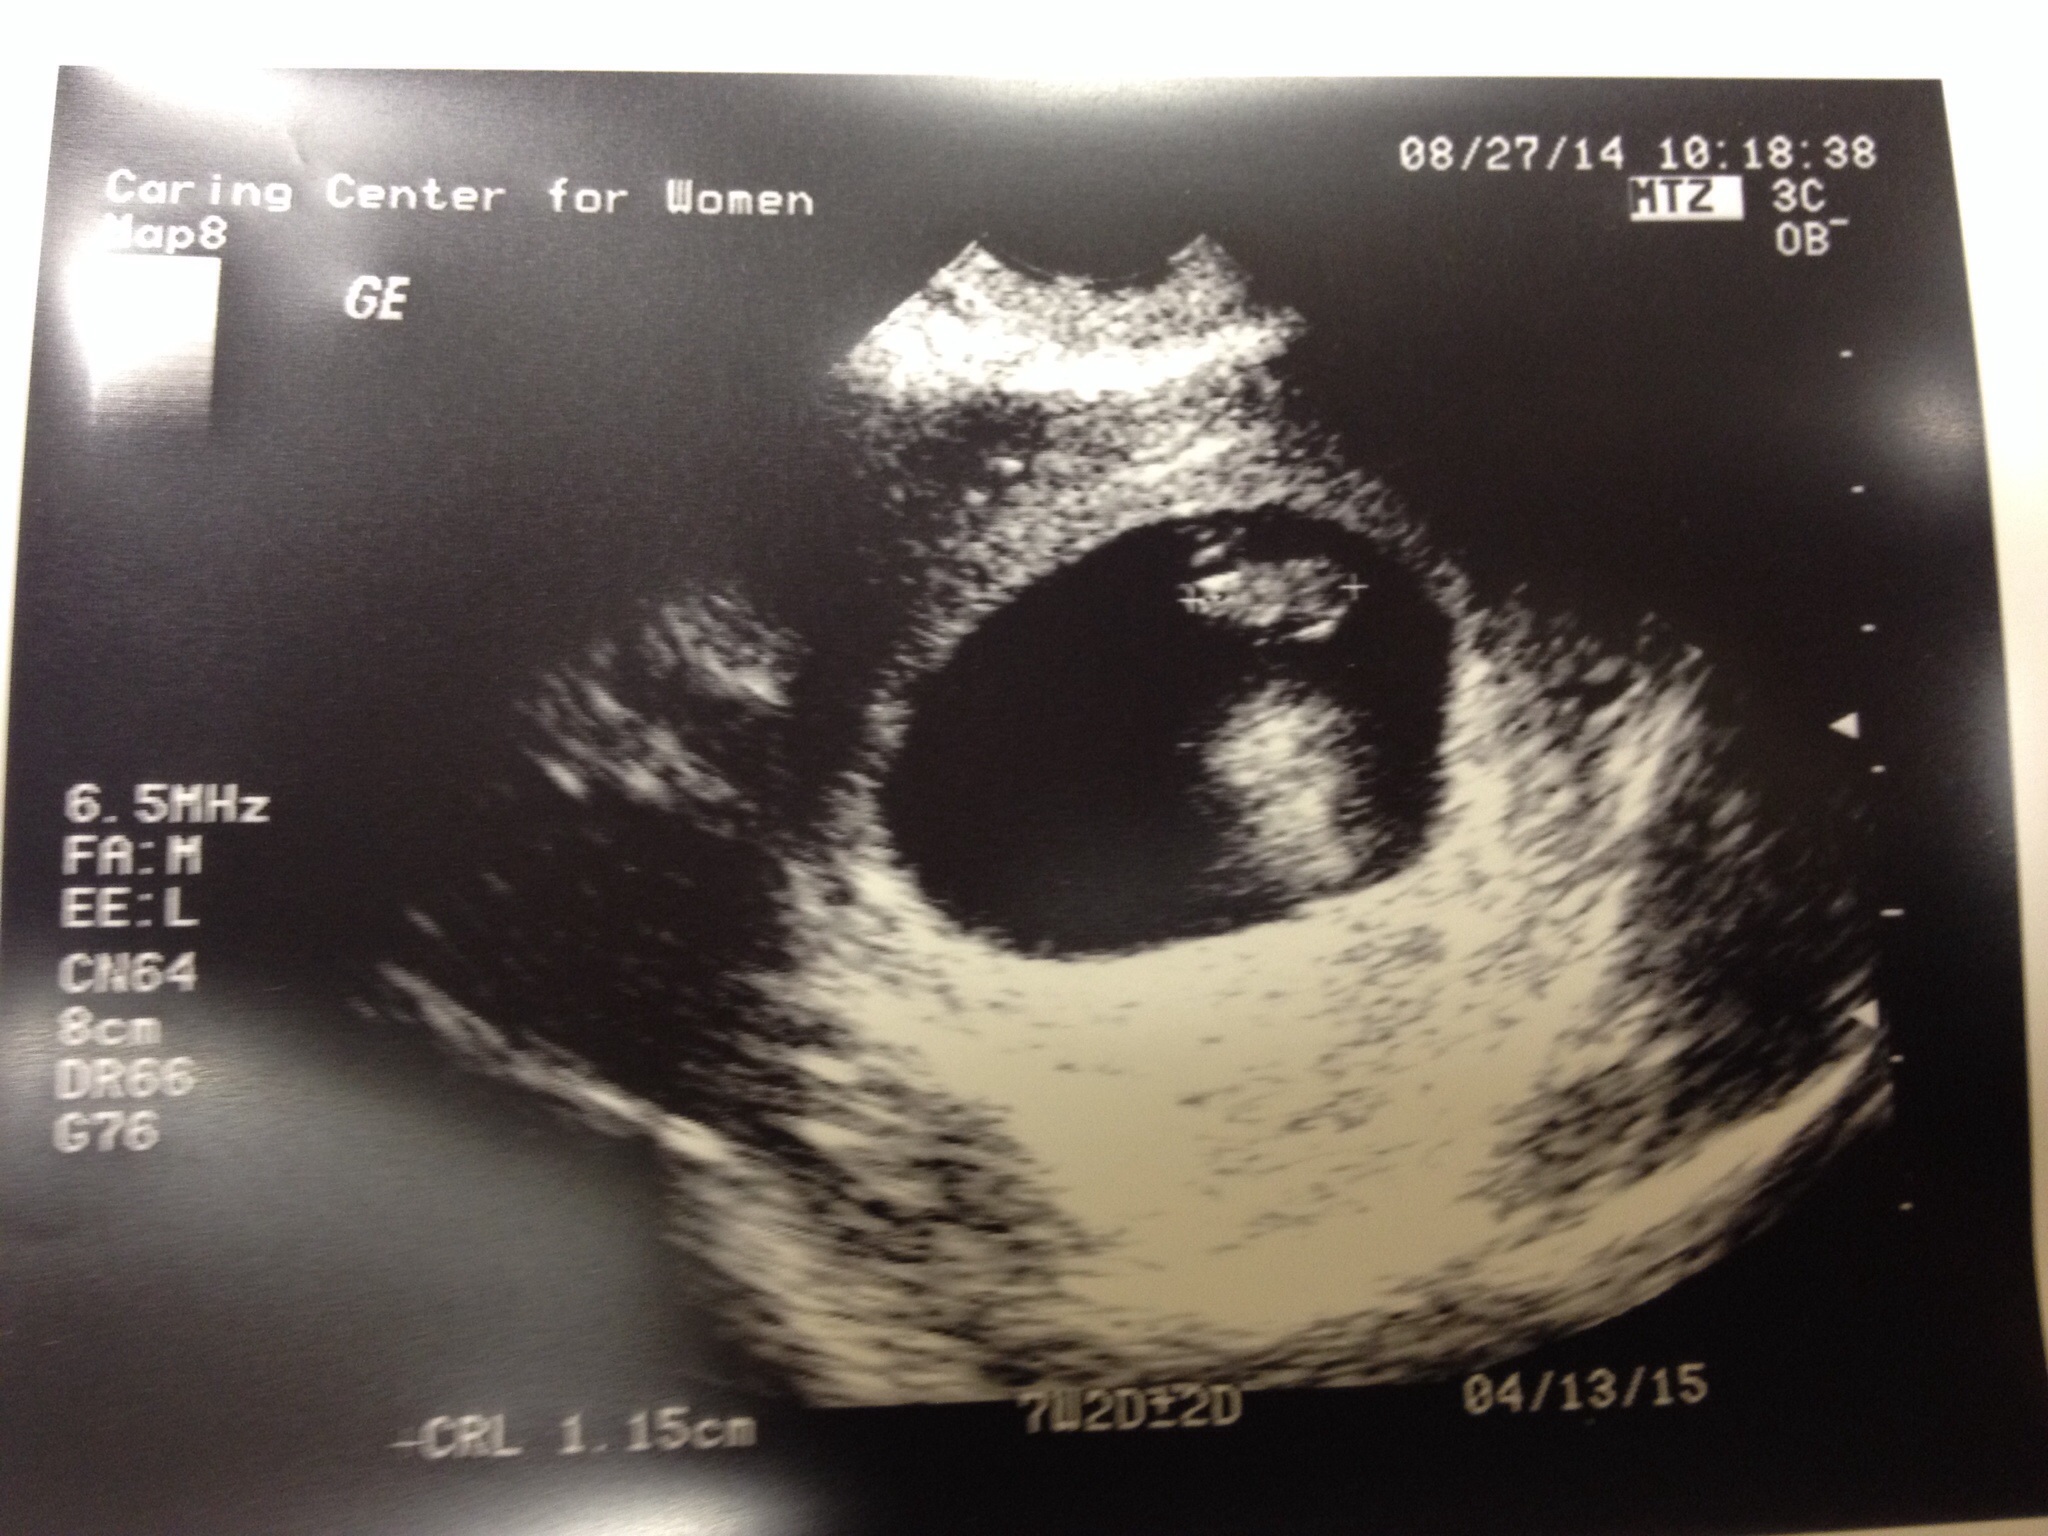

• Saw ours two weeks ago at 5w6d then went two days ago for dating ultrasound and they picked it up at 167bpm but still didn't get to hear it yet

image